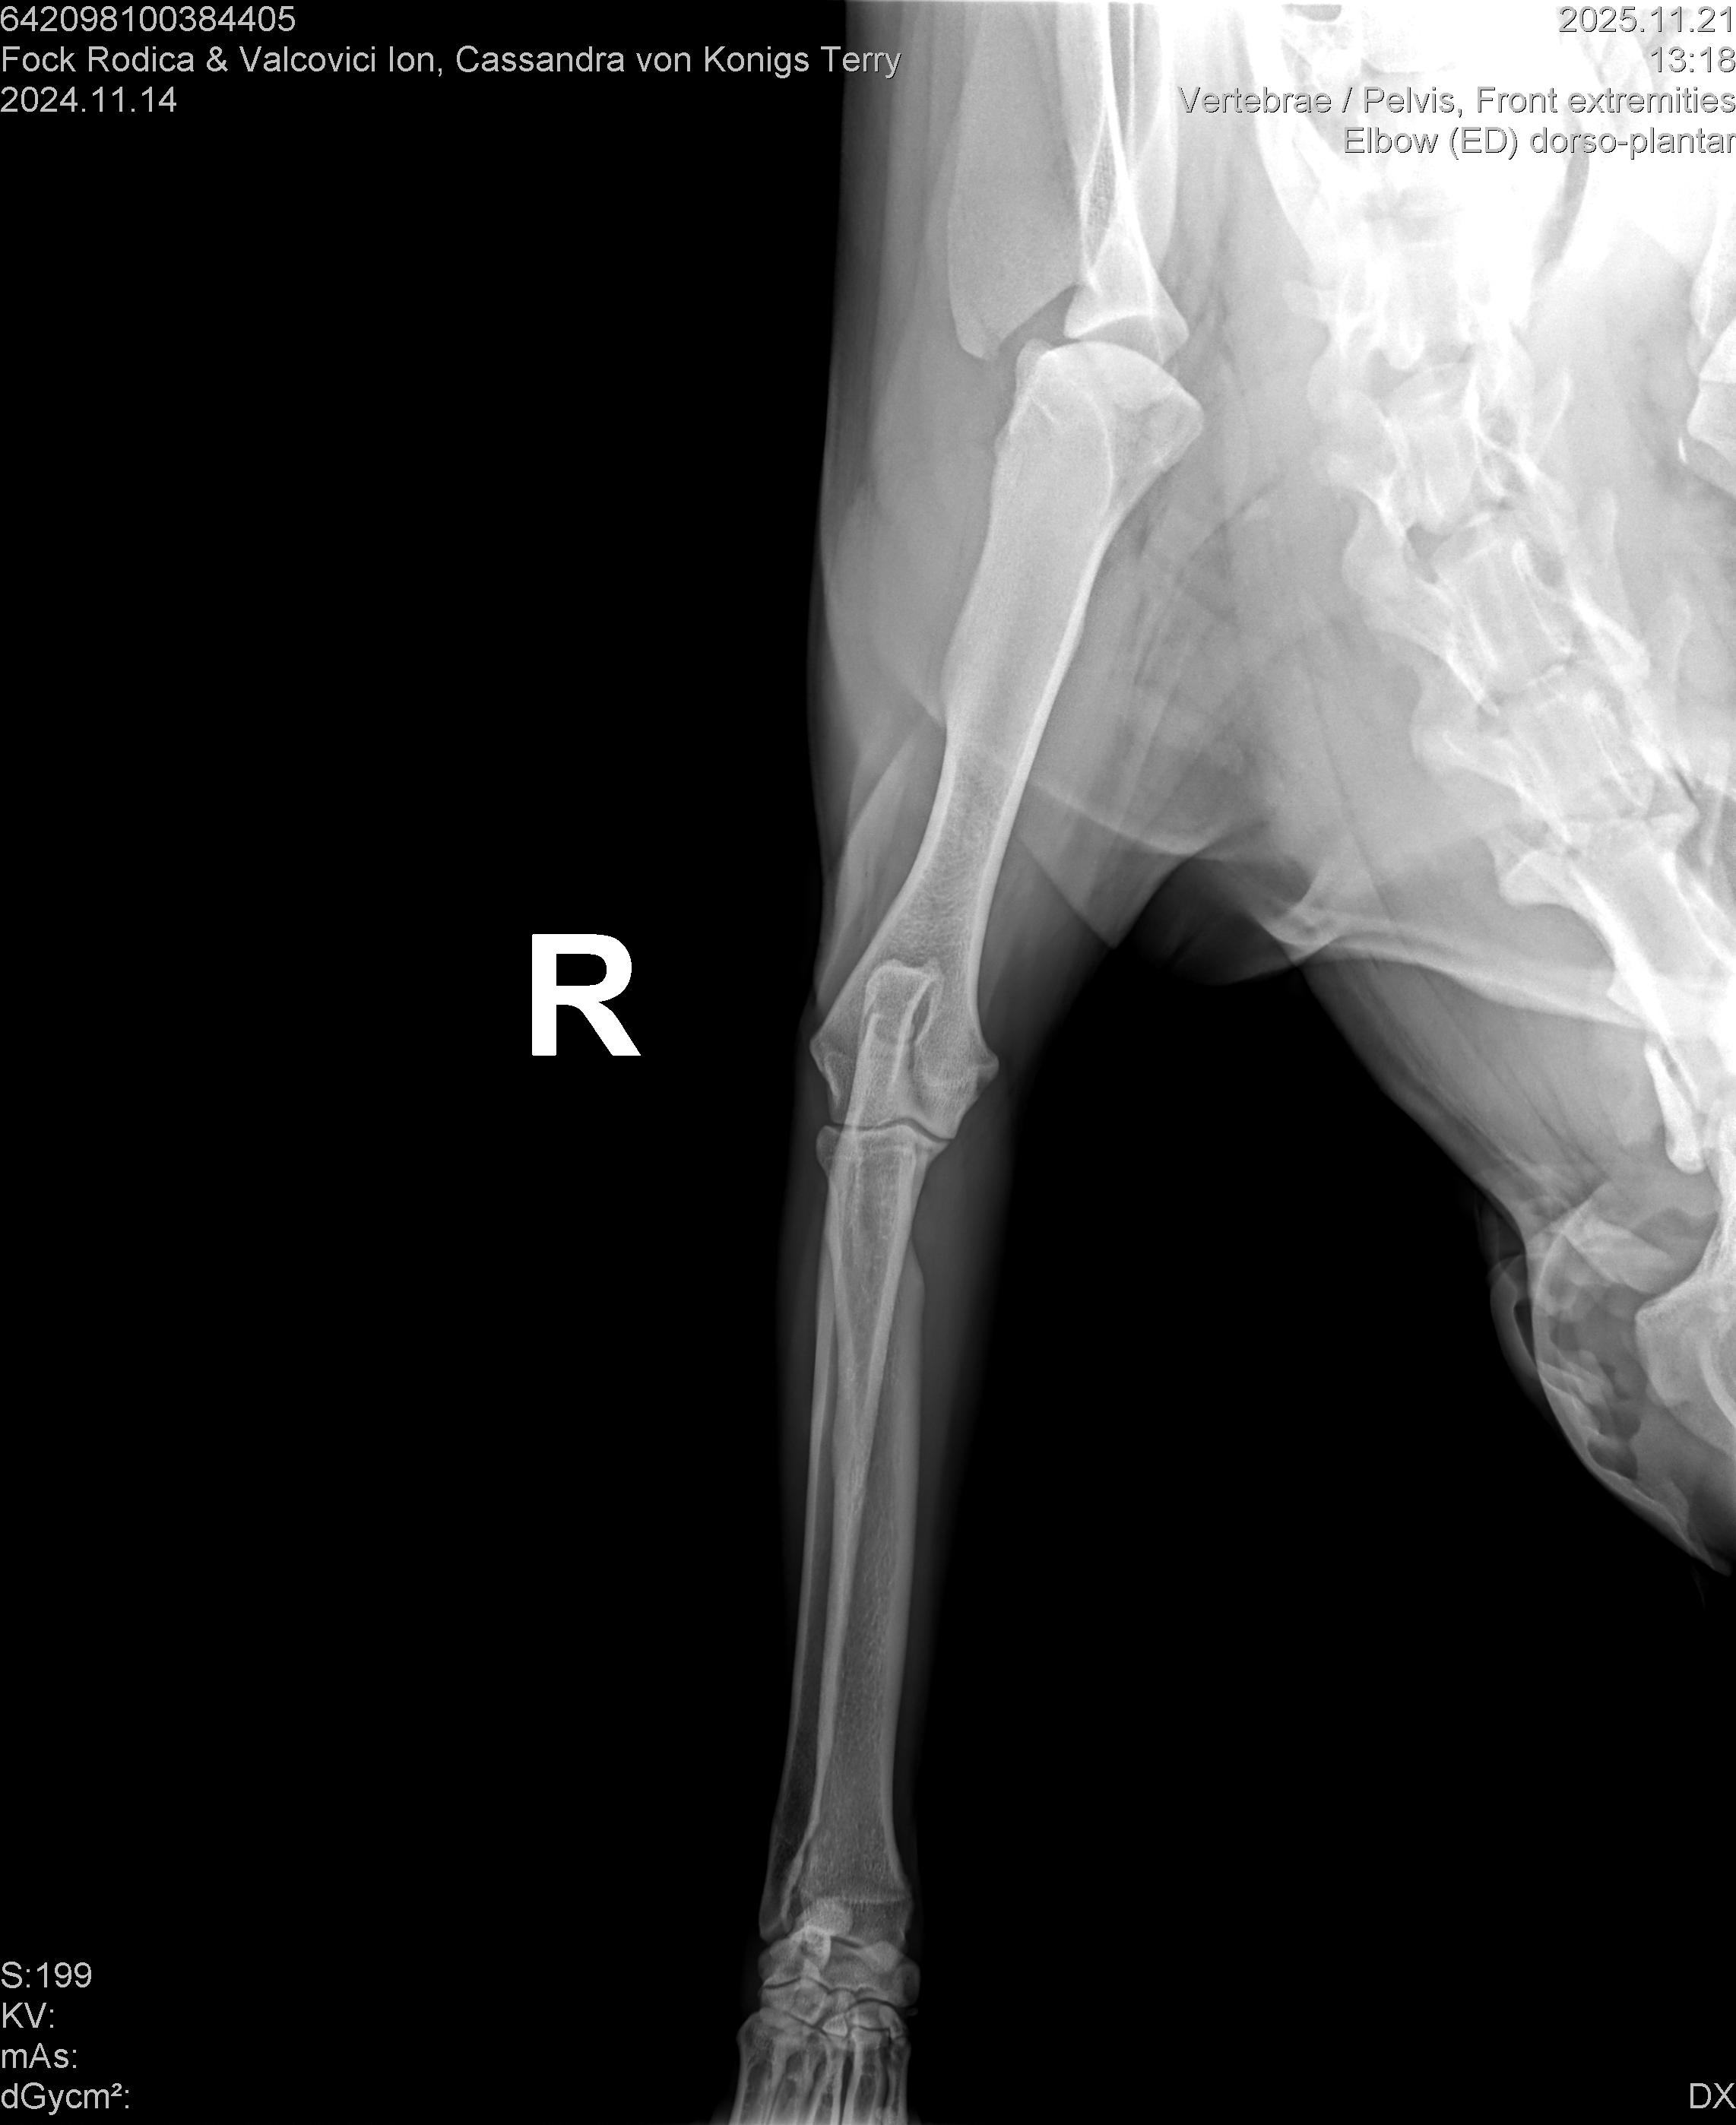

CASSANDRA VON KONIGS-TERRY

( CASSY )

Data nasterii:

14.11.2024

Crescator:

FOCK RODICA si VALCOVICI ION